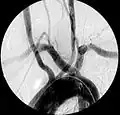

| Aberrant subclavian artery on MR angiography. | |

Magnetic Resonance Imaging (MRI): MRI or MR angiography can similarly detail the vascular anatomy and is often used in children to reduce radiation exposure.

Aberrant right subclavian artery at angiography.